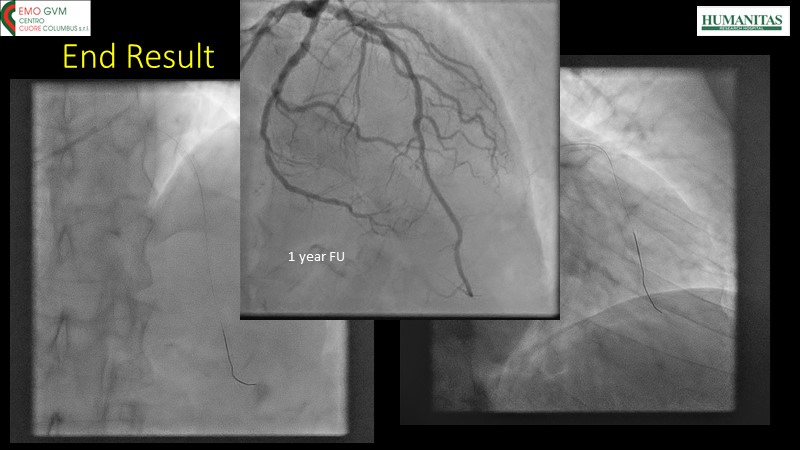

- To know why sirolimus coated balloon is the ideal choice in native vessel disease treatment through a case presentation